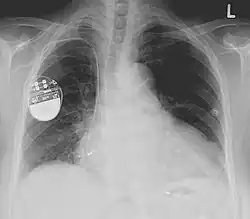

Kardiostimulátor je malá kovová krabička, z níž vycházejí jedna až tři elektrody. Stimulátor vytváří elektrické výboje, které jsou následně prostřednictvím elektrod přenášeny na srdeční svalovinu, kde iniciují srdeční kontrakci. Frekvenci takovýchto signálů lze upravit podle potřeby pacienta.

Elektrody se do srdce zavádějí pod rentgenovou kontrolou z krátkého řezu pod klíční kosti cestou v. subclavia. Po zavedení elektrod je kardiostimulátor implantován do podkoží do místa původního řezu (infraklavikulární oblasti). Vzniklá rána se sešívá vstřebatelným materiálem. Vzhledem k tomu, že krabička stimulátoru není zavedena hluboko, je vidět jako vyklenutí kůže a pacient si ji může lehce nahmatat.